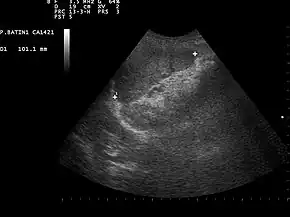

![]() Ultrasound image of a normal spleen that may be seen in part of the eFAST | |

Focused assessment with sonography in trauma (commonly abbreviated as FAST) is a rapid bedside ultrasound examination performed by surgeons, emergency physicians, and paramedics as a screening test for blood around the heart (pericardial effusion) or abdominal organs (hemoperitoneum) after trauma.[1][2] There is also the extended FAST (eFAST) which includes some additional ultrasound views to assess for pneumothorax.[3][4]

- Left Upper Quadrant of the abdomen (Perisplenic view). Left upper quadrant is examined by working your probe down the midaxillary line starting at the left 8th rib to the 11th rib. This examines for free fluid around the kidney and spleen.